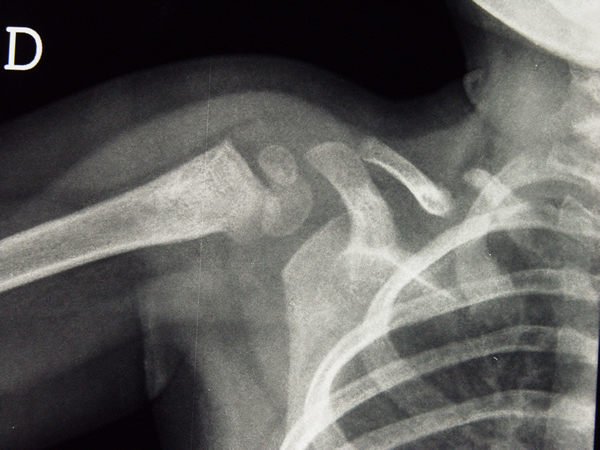

In ogni modo sembrava che le cose stessero proprio cos� e la radiografia di controllo, eseguita dopo sette giorni, veniva refertata in questo modo: �Soddisfacente l'allineamento dei frammenti di frattura della metafisi prossimale dell'omero. Sostanzialmente immodificati i reperti a carico della clavicola, dove non si evidenzia sicura presenza di callo osseo anche a causa dell'apparecchio gessato�. Una nuova radiografia, eseguita al 32� giorno, era cos� descritta: �Esiti di frattura della metafisi prossimale dell'omero consolidata in posizione soddisfacente. Invariato l'aspetto dei monconi diasassiati della clavicola compatibili con la diagnosi di pseudo-artrosi� (figura 2).

I segni radiologici sono abbastanza caratteristici: i margini dei monconi sono smussi, arrotondati, claveati, ipercaptanti, ma, soprattutto, i bordi dei due capi non collimano come succede nel caso di un vera frattura (4).